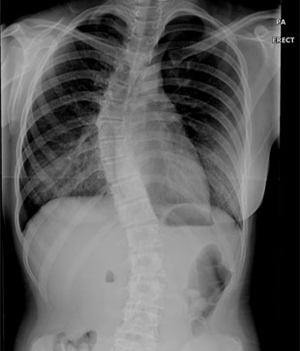

<ôÃßÃø¸¸ÁõȯÀÚ X-RAY>

Á¤»óÀûÀΠôÃß´Â Á¤¸é¿¡¼­ º¸¾ÒÀ» ¶§ ÀÏÁ÷¼±ÀÌ¸ç ¿·¿¡¼­ º¸¾ÒÀ» ¶§¿¡´Â °æÃß¿Í ¿äÃß´Â ¾ÕÀ¸·Î ÈÖ¾î ÀÖ°í ÈäÃß¿Í ÃµÃߺδ µÚ·Î ÈÖ¾î ÀÖ½À´Ï´Ù.

º¸Åë ôÃß°¡ 10µµÀÌ»ó ÈÖ¾î ÀÖ´Â °æ¿ì¸¦ Ãø¸¸ÁõÀ̶ó°í Çϸç 40µµ ÀÌ»ó ÈÖ¾îÀÖ´Â °æ¿ì¿¡´Â ±³Á¤Ä¡·á¸¸À¸·Î ÇØ°áÀÌ ¾î·Á¿ï ¼ö ÀÖ½À´Ï´Ù.